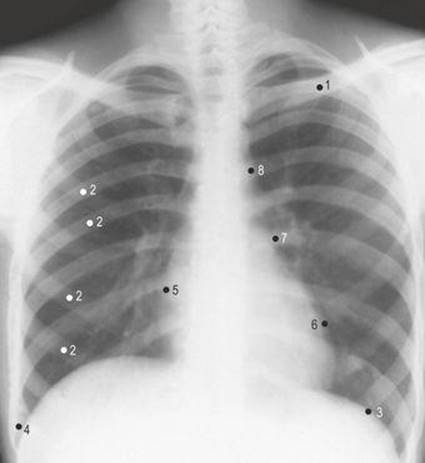

4.4 Chest radiograph: anterior view

1 Clavicle

2 Ribs

3 Left dome of diaphragm

4 Right costophrenic angle

5 Right border of heart

6 Left border of heart

7 Pulmonary conus

8 Aortic knuckle